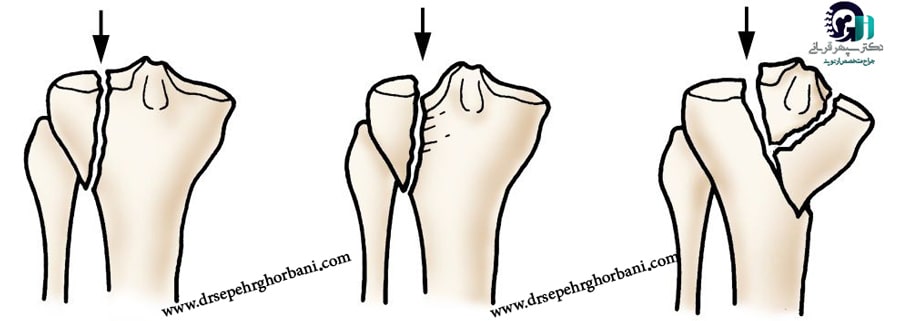

شکستگی تیبیا انواع مختلفی داره که هر کدوم ویژگیها و روشهای درمان متفاوتی دارن. شناخت نوع شکستگی به پزشک کمک میکنه بهترین راه درمان رو انتخاب کنه. اصلیترین انواع شکستگی تیبیا عبارتاند از:

۲. شکستگی ساده و چندتکه

-

شکستگی ساده: استخوان فقط در یک محل شکسته و قطعات آن به هم چسبیدهاند.

-

شکستگی چندتکه (خرد شده): استخوان در چند بخش شکسته و قطعات استخوان از هم جدا شدهاند.

۳. شکستگی خطی، مارپیچی و قطعی

-

شکستگی خطی: شکستگی به صورت یک خط مستقیم در طول استخوان ایجاد میشود.

-

شکستگی مارپیچی: شکستگی به صورت پیچخورده است که معمولاً به علت چرخش یا پیچش ناگهانی ایجاد میشود.

-

شکستگی قطعی (Transverse): شکستگی به صورت خطی عمود بر محور استخوان است.